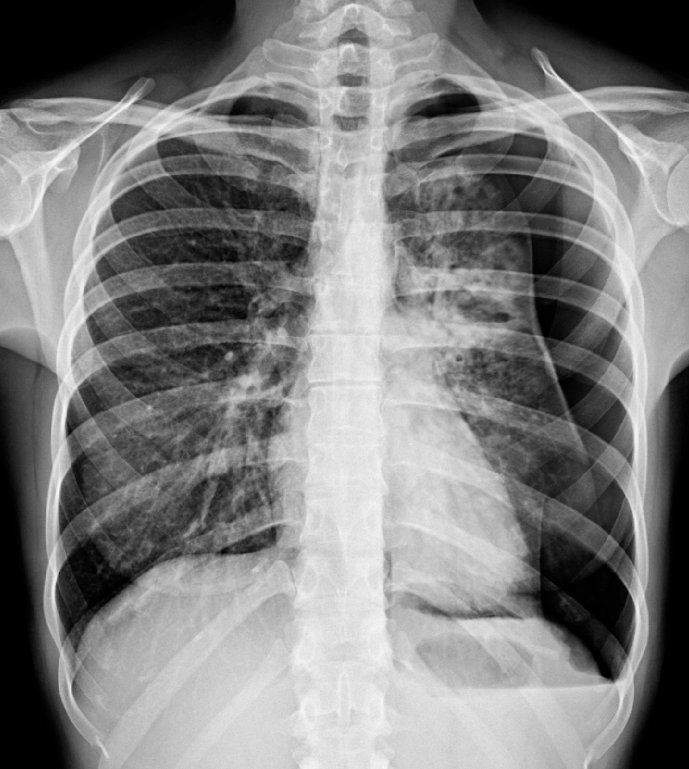

Chest radiography, ultrasonography, or CT can be used for diagnosis, although diagnosis from a chest x-ray is more common. Radiographic findings of a 2.5 cm air space are equivalent to a 30% pneumothorax.